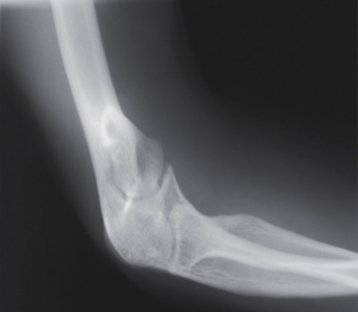

lateral elbow

What projection, position, and anatomy is this?